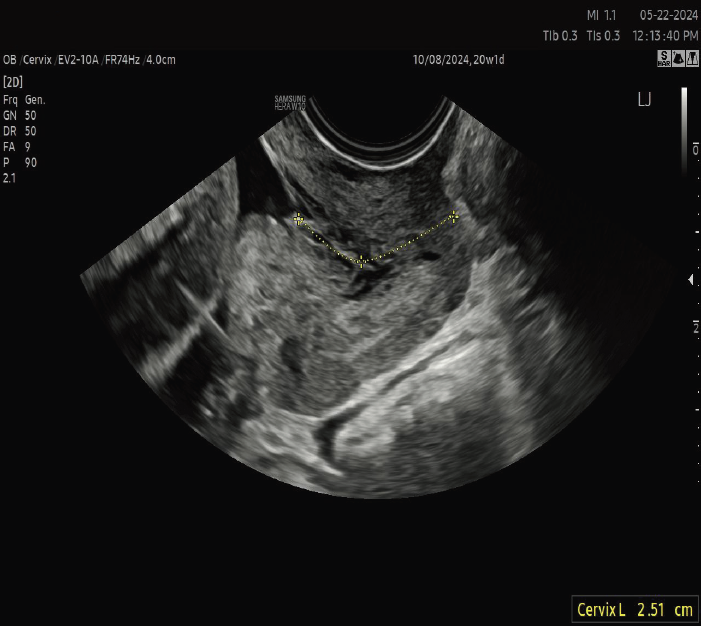

An ultrasound-indicated cerclage is a wise choice when a woman’s cervical length measures less than 24 mm, particularly if she has a history of spontaneous preterm births or mid-trimester losses. Significantly, for those expecting twins, the threshold for intervention is even shorter, with cervical lengths under 15 mm suggesting the need for this supportive measure.

Regular cervical length monitoring is another vital aspect of managing this condition, ensuring any changes are promptly detected. It's crucial to have an in-depth discussion with healthcare providers about these treatments, enabling patients to make the most informed and personalized decisions for their health and their baby's well-being.